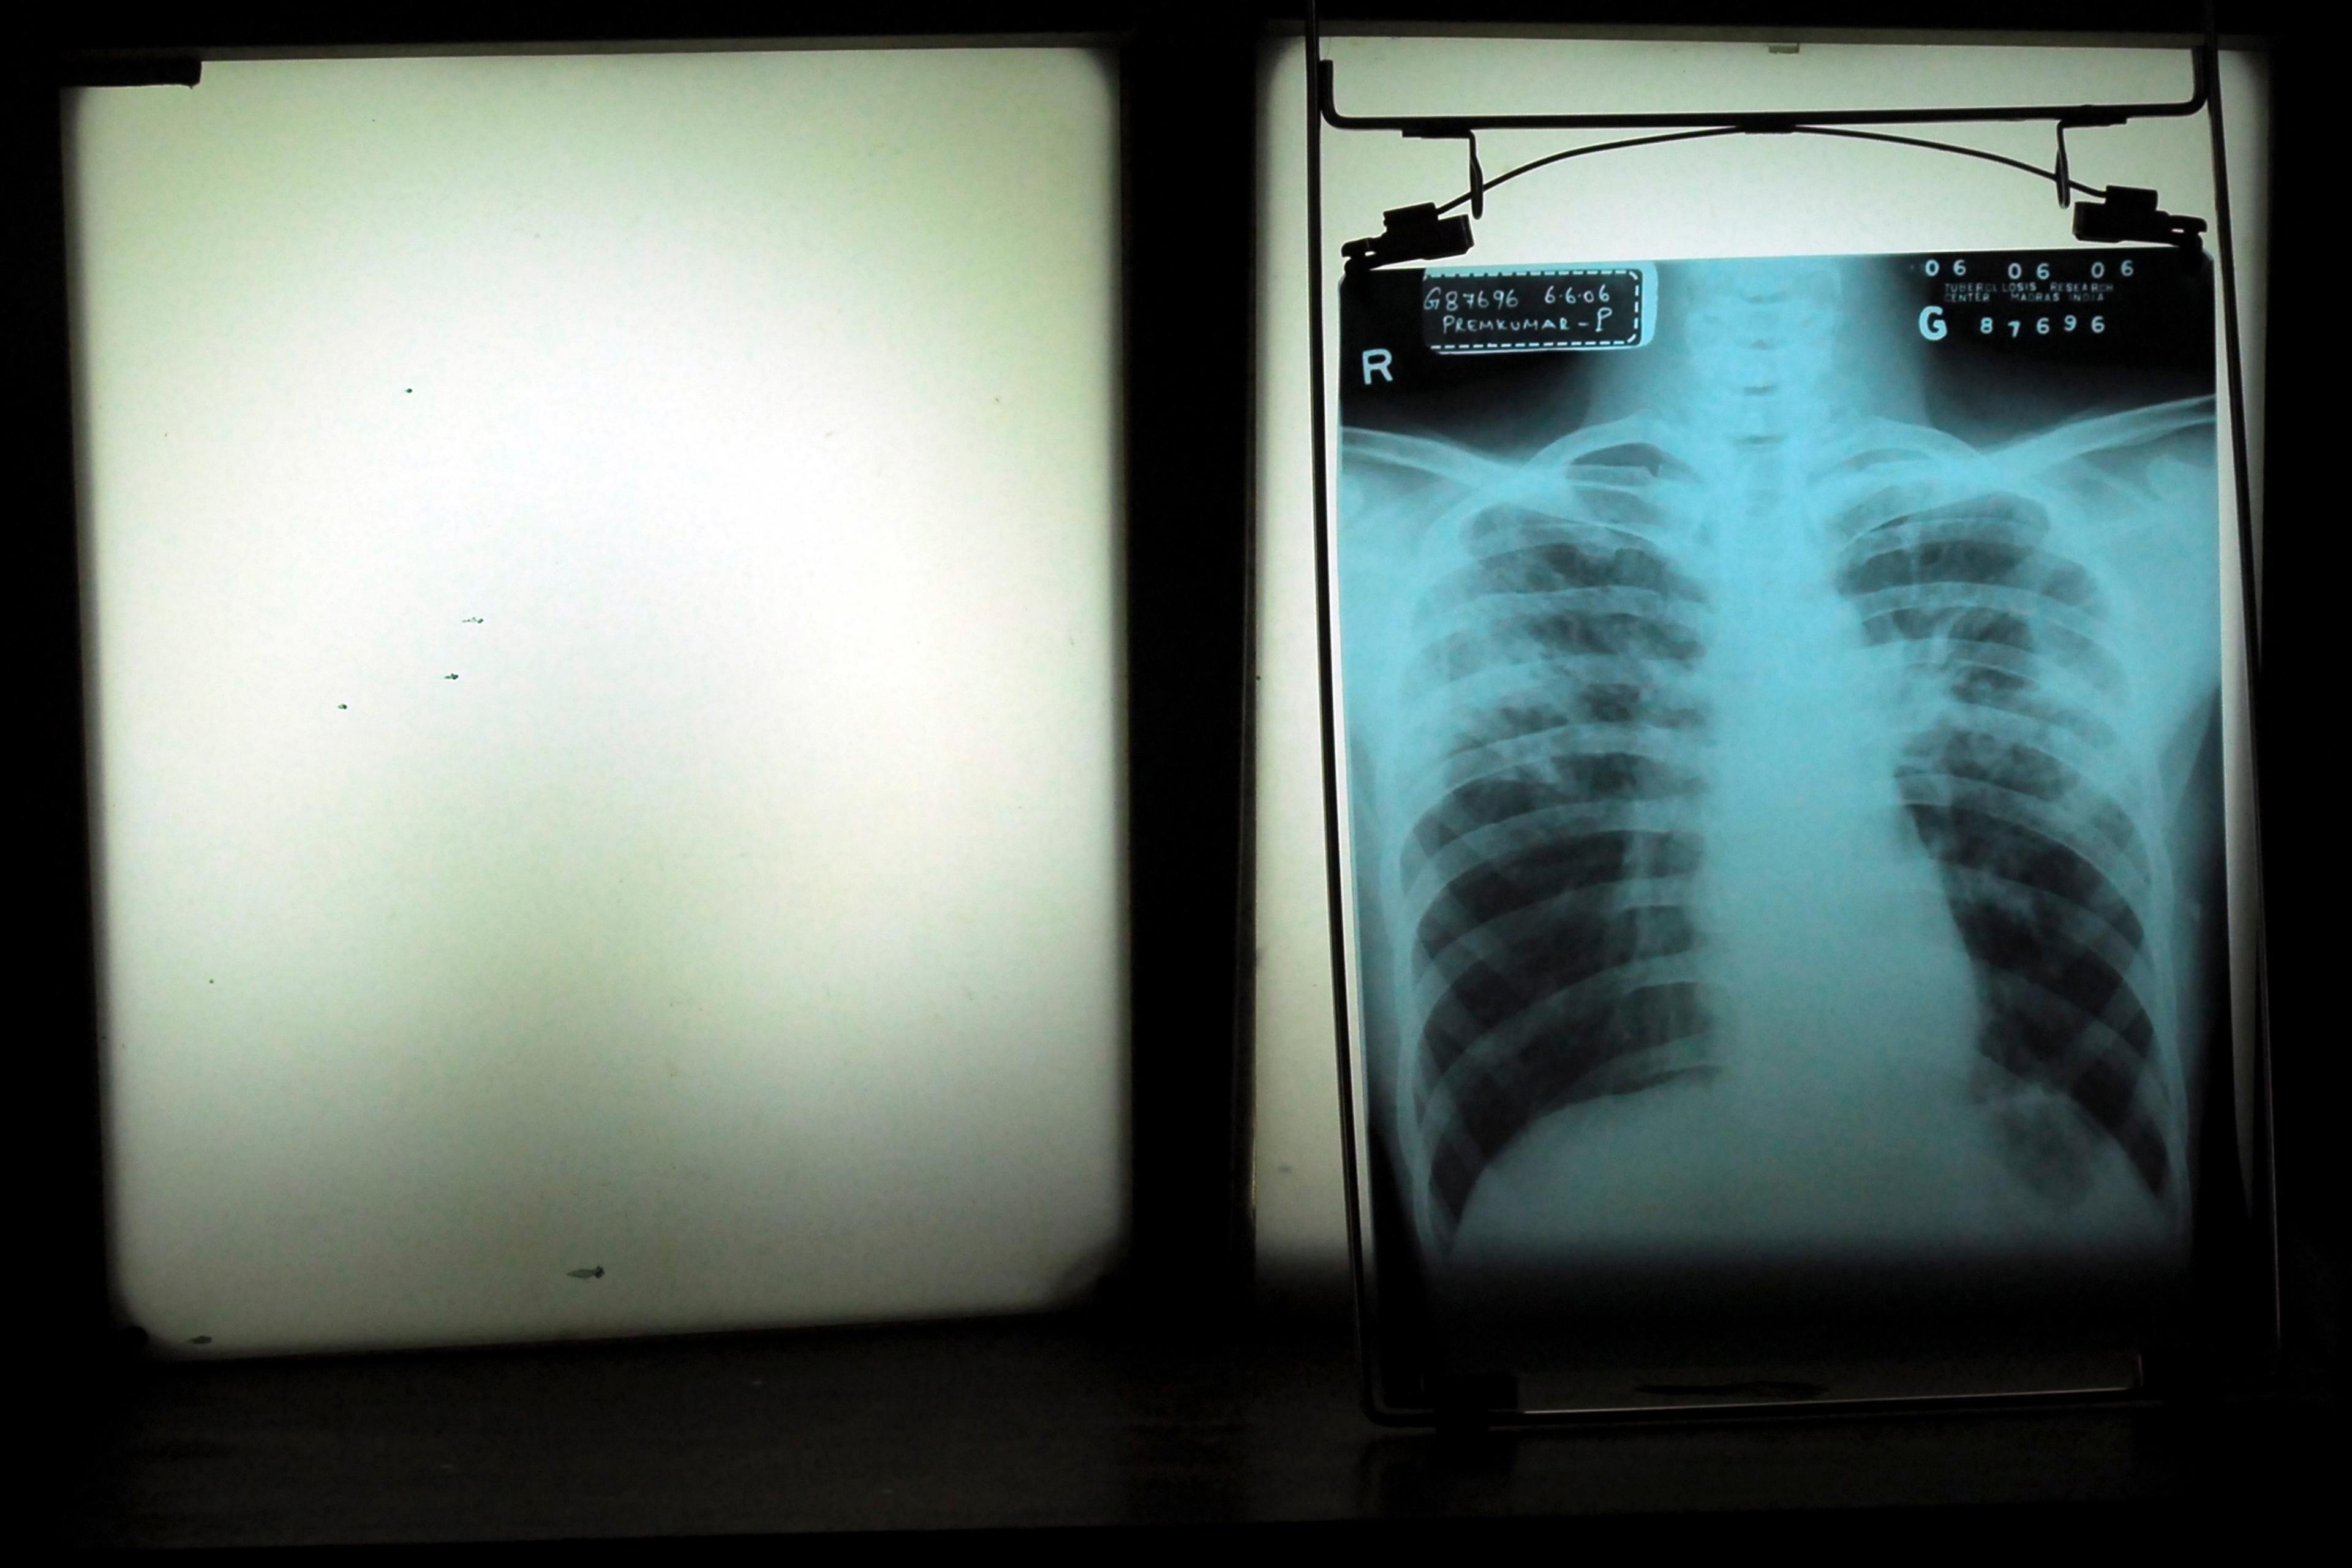

Studying tuberculosis in India, I saw the problem with cures

The ideal cure, a return to before the disorder or disease, can happen. But often that’s just not how bodies and life work